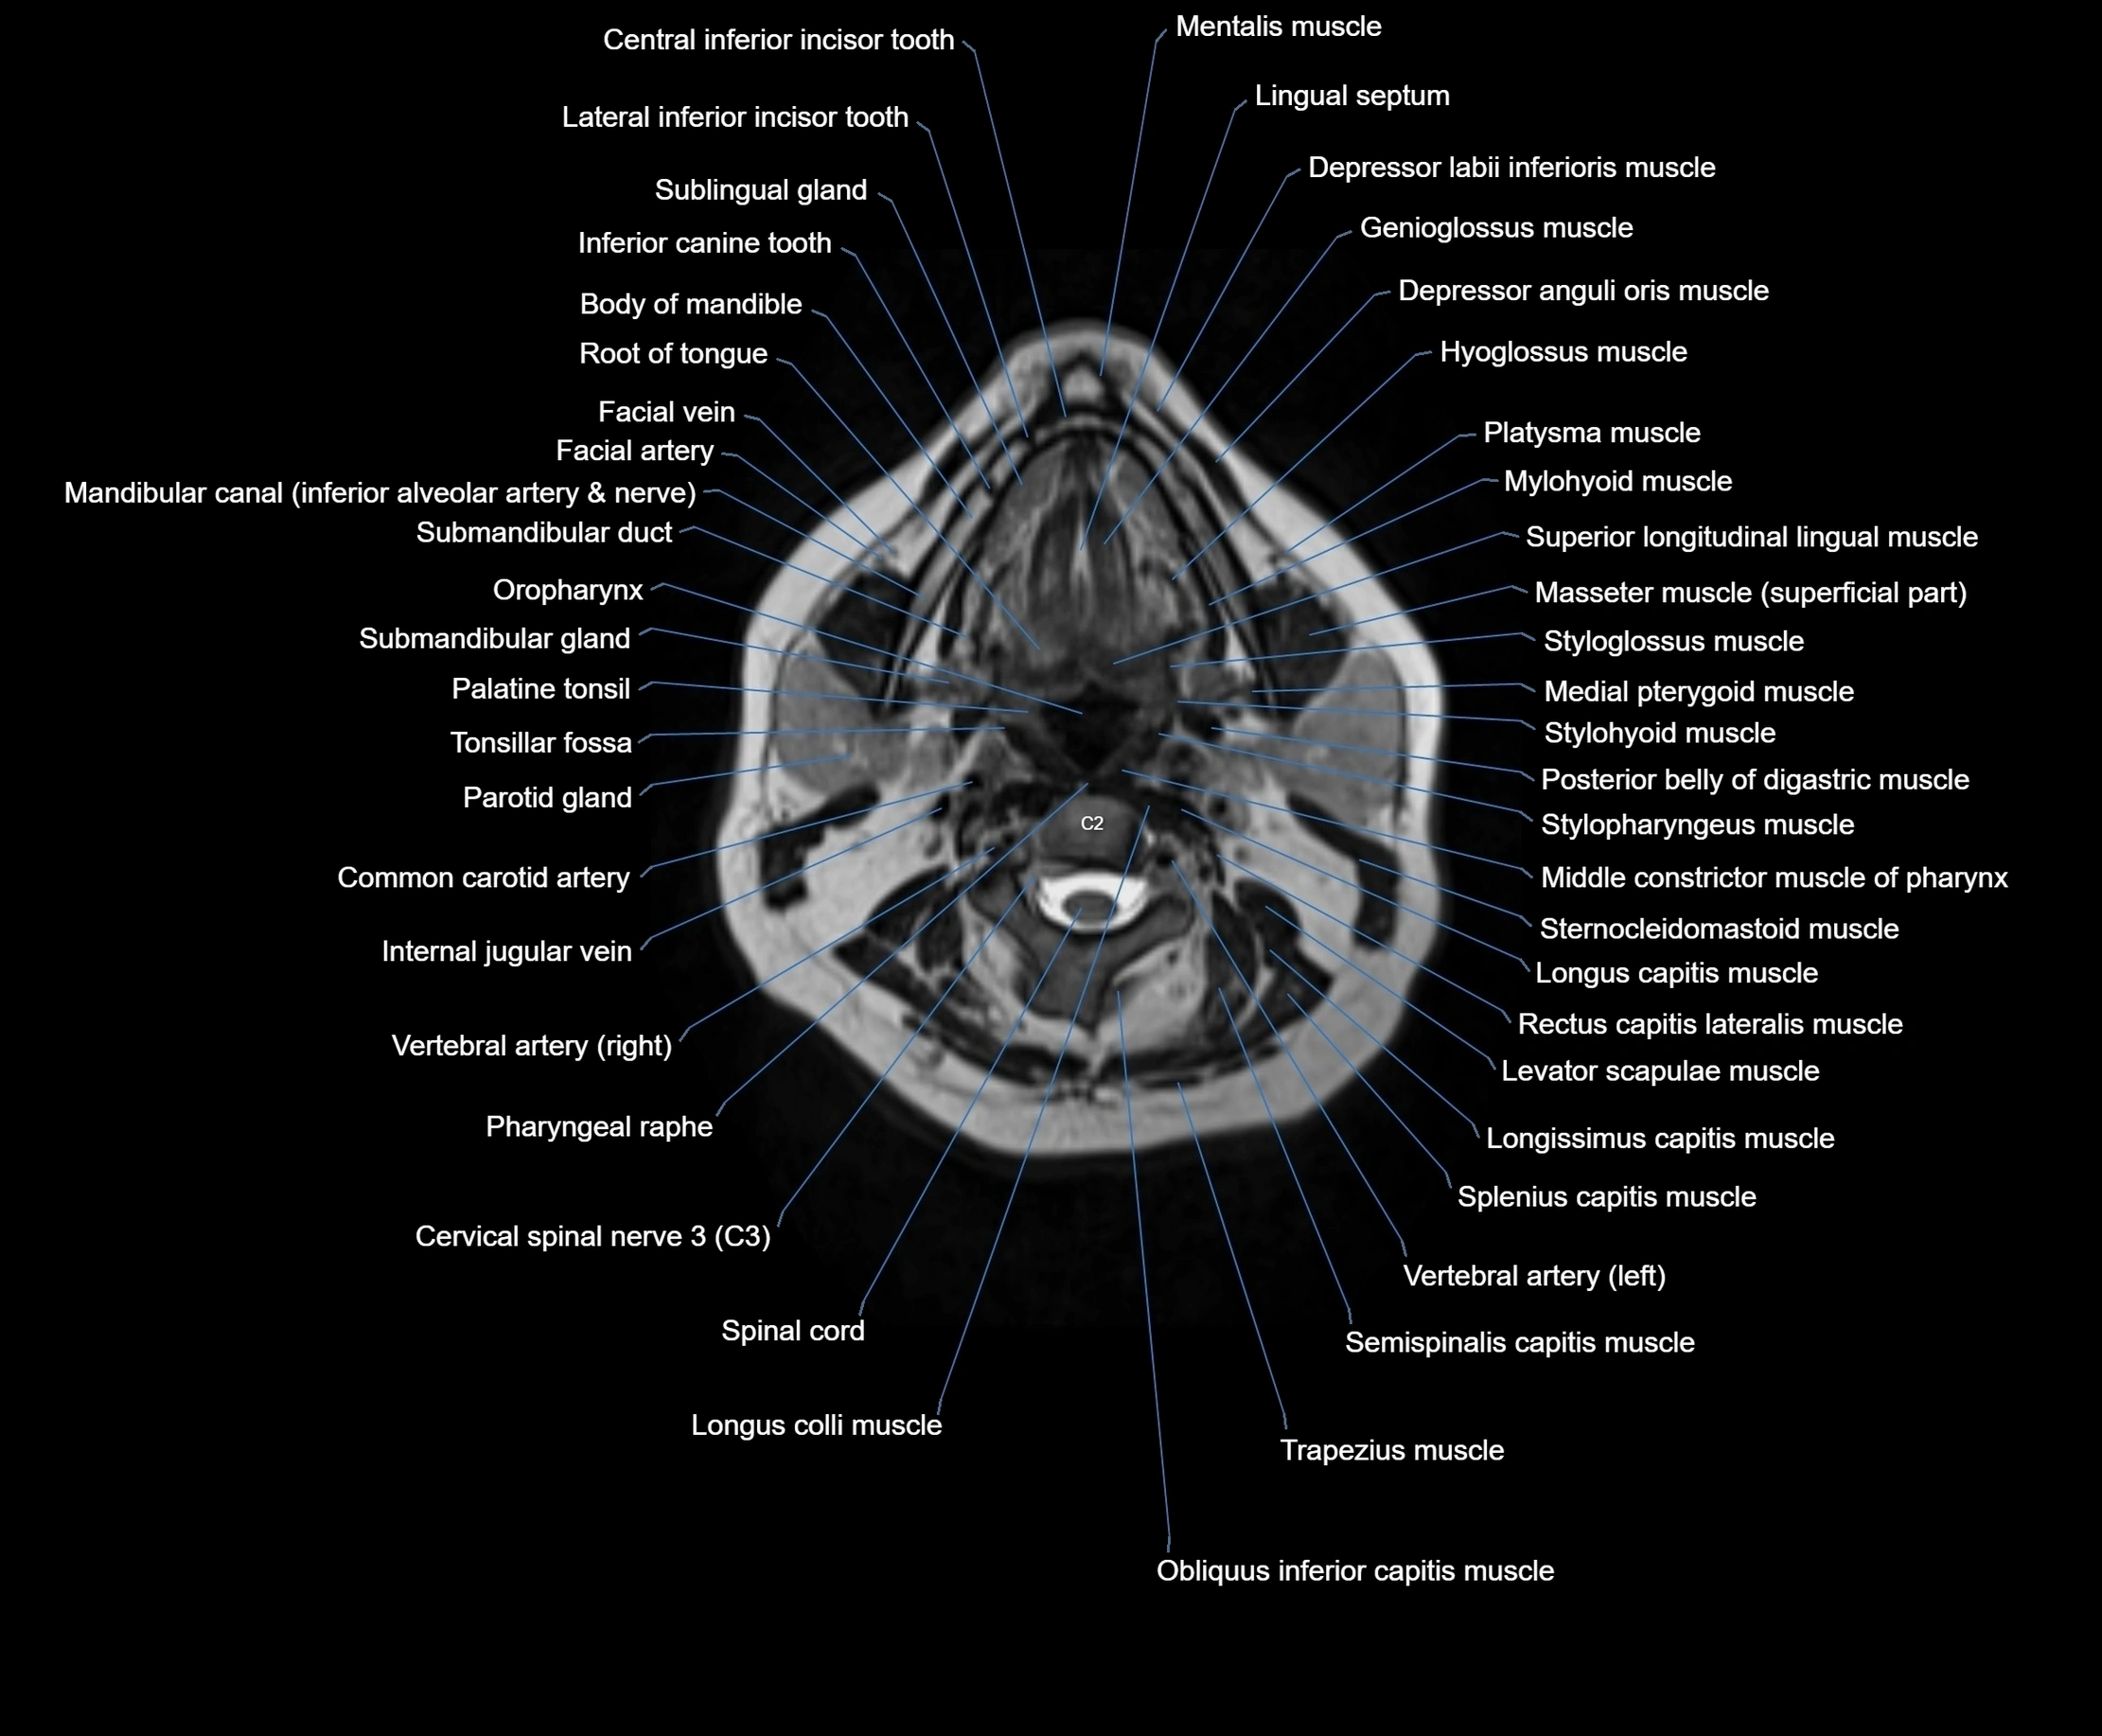

MRI images